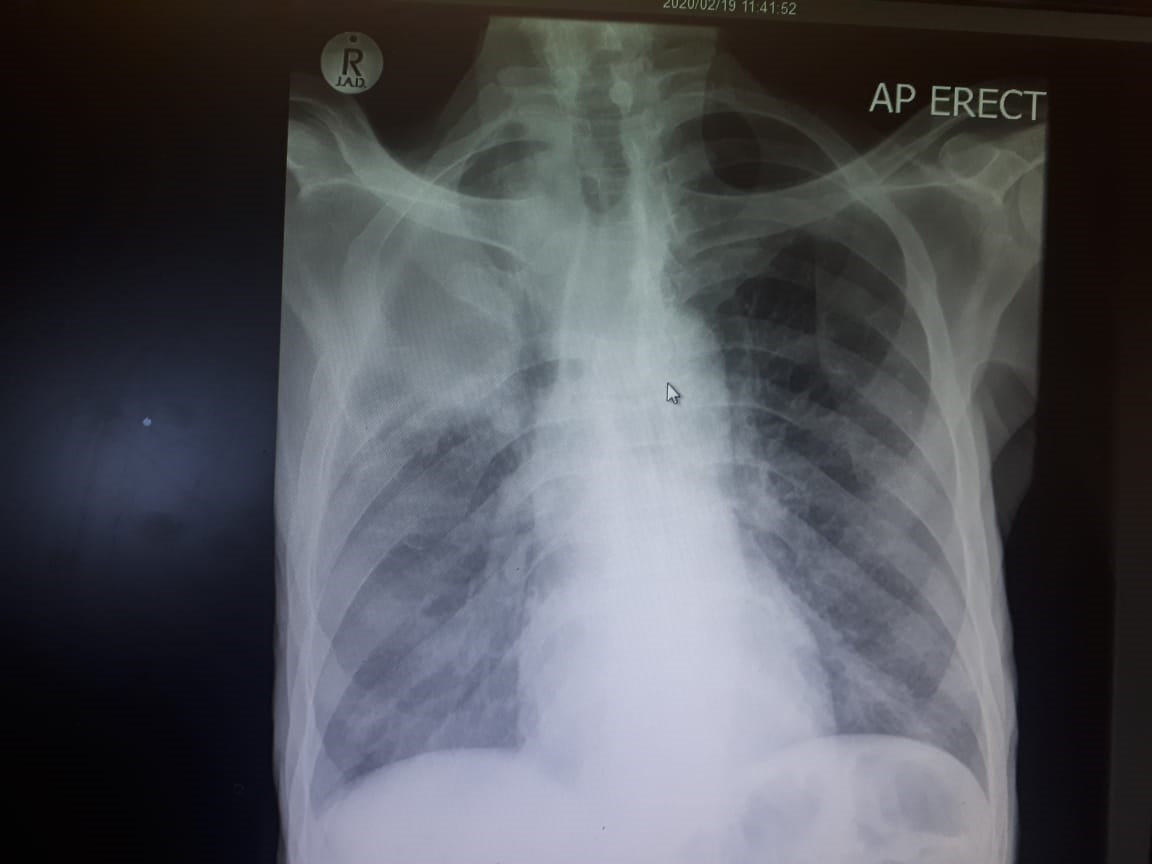

A classic case of Cushing Disease

HOSP # 165965617 WARD Endocrine Ward CONSULTANT   Dr Heleen Vreede DOB/AGE 33 y female Abnormal Result Salivary Cortisol = 36 nmol/L Presenting Complaint Struggling with a right hand abscess –